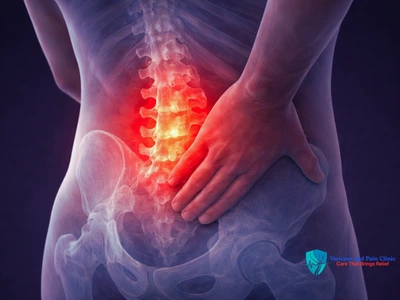

Back Pain Treatment